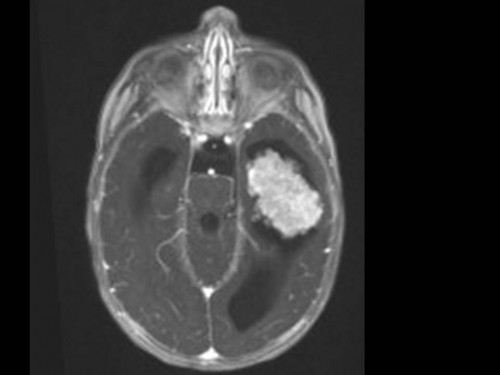

10 Monate altes Mädchen. Der Kinderarzt stellt fest, dass das kleine Mädchen einen recht großen Kopfumfang hat, nicht mit den Augen fixiert und anscheinend auch nicht richtig sehen kann. Damit bestätigt er die größten Befürchtungen der Eltern, denen in den letzten Wochen aufgefallen war, dass ihre Tochter nach keinem Spielzeug mehr greift und sie nur dann anlächelt, wenn sie zu ihr sprechen.

Bildgebung - MRT